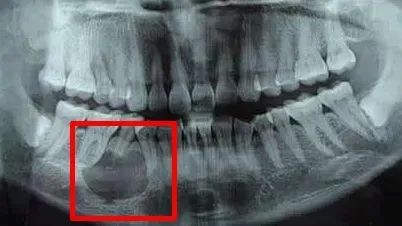

▲根尖囊肿,会引起周围骨质的吸收,脸部会慢慢出现畸形的状态。